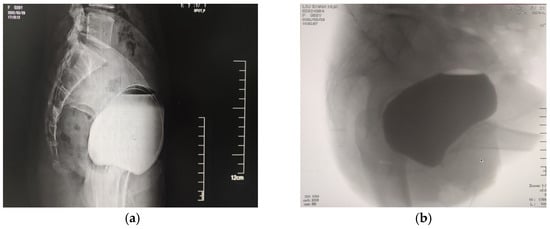

- Pelsang, R.E.; Bonney, W.W. Voiding cystourethrography in female stress incontinence. Am. J. Roentgenol. 1996, 166, 561–565. [Google Scholar] [CrossRef][Green Version]

- Grob, A.T.M.; Olde Heuvel, J.; Futterer, J.J.; Massop, D.; Veenstra van Nieuwenhoven, A.L.; Simonis, F.F.J.; van der Vaart, C.H. Underestimation of pelvic organ prolapse in the supine straining position, based on magnetic resonance imaging findings. Int. Urogynecol. J. 2019, 30, 1939–1944. [Google Scholar] [CrossRef] [PubMed]

- Thind, P.O.; Lose, G. [Use of micturition cystourethrography in evaluation of urinary incontinence in women]. Ugeskr. Laeger 1990, 152, 2095–2098. [Google Scholar] [PubMed]

- Varpula, M.; Mäkinen, J.; Kiilholma, P. Cough urethrocystography: The best radiological evaluation of female stress urinary incontinence? Eur. J. Radiol. 1989, 9, 191–194. [Google Scholar] [PubMed]

- Kelvin, F.M.; Maglinte, D.D.; Hale, D.; Benson, J.T. Voiding cystourethrography in female stress incontinence. Am. J. Roentgenol. 1996, 167, 1065–1066. [Google Scholar] [CrossRef]

- Bergman, A.; McKenzie, C.; Ballard, C.A.; Richmond, J. Role of cystourethrography in the preoperative evaluation of stress urinary incontinence in women. J. Reprod. Med. 1988, 33, 372–376. [Google Scholar]